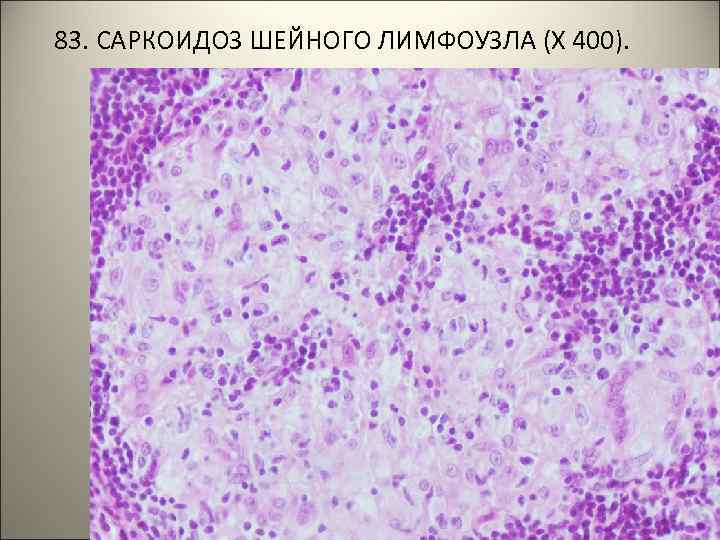

• 83. САРКОИДОЗ ШЕЙНОГО ЛИМФОУЗЛА. • В ткани лимфоузла множественные гранулемы, состоящие из эпителиоидных, лимфоидных, единичных гигантских клеток. Творожистый некроз отсутствует, границы гранулем четкие (т. н. «штампованные» гранулемы).

83. САРКОИДОЗ ШЕЙНОГО ЛИМФОУЗЛА (Х 100).

83. САРКОИДОЗ ШЕЙНОГО ЛИМФОУЗЛА (Х 400).